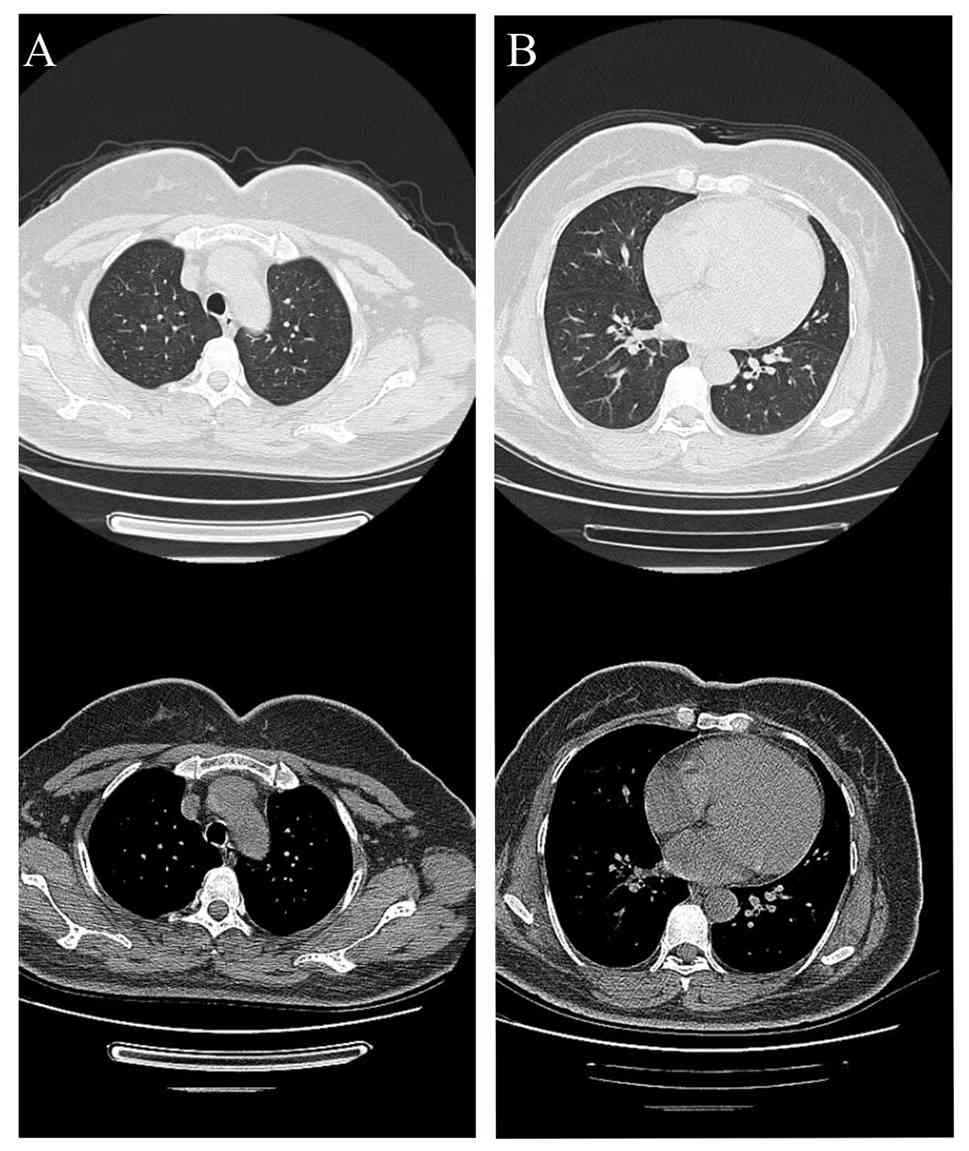

Follow-up chest CT images from

November 2023, 1 month following admission. (A) Lung and

mediastinal windows of the upper lung lobes. (B) Lung and

mediastinal windows of the lower lung lobes. The patchy/nodular

opacities observed in Fig. 1 were

completely resolved.

Figure 4

Follow-up chest CT images from November 2023, 1 month following admission. (A) Lung and mediastinal windows of the upper lung lobes. (B) Lung and mediastinal windows of the lower lung lobes. The patchy/nodular opacities observed in Fig. 1 were completely resolved.

In the present case report, insulin was administered to maintain optimal blood glucose control. While awaiting diagnostic results, empirical moxifloxacin therapy was initiated for CAP. Once mNGS identified T. whipplei as the causative pathogen, the patient indicated notable clinical improvement within 1 week and moxifloxacin was continued as a short-term treatment. Following discharge, the patient completed a 1-week course of oral moxifloxacin and remained stable. A follow-up chest CT scan 1 month later indicated complete resolution of the bilateral opacities. The patient's condition continued to improve and the patient declined further chest CT scans. Although moxifloxacin is not a guideline-recommended treatment for T. whipplei infection, its short-term use in the present case was reasonable given the acute presentation of the patient, the absence of other pathogens and the requirement for prompt therapy. Despite the favorable response, evidence supporting fluoroquinolone monotherapy for T. whipplei infection remains limited (16,17). Further studies are needed to evaluate the efficacy and durability of such regimens and to establish optimal treatment strategies for T. whipplei infections.